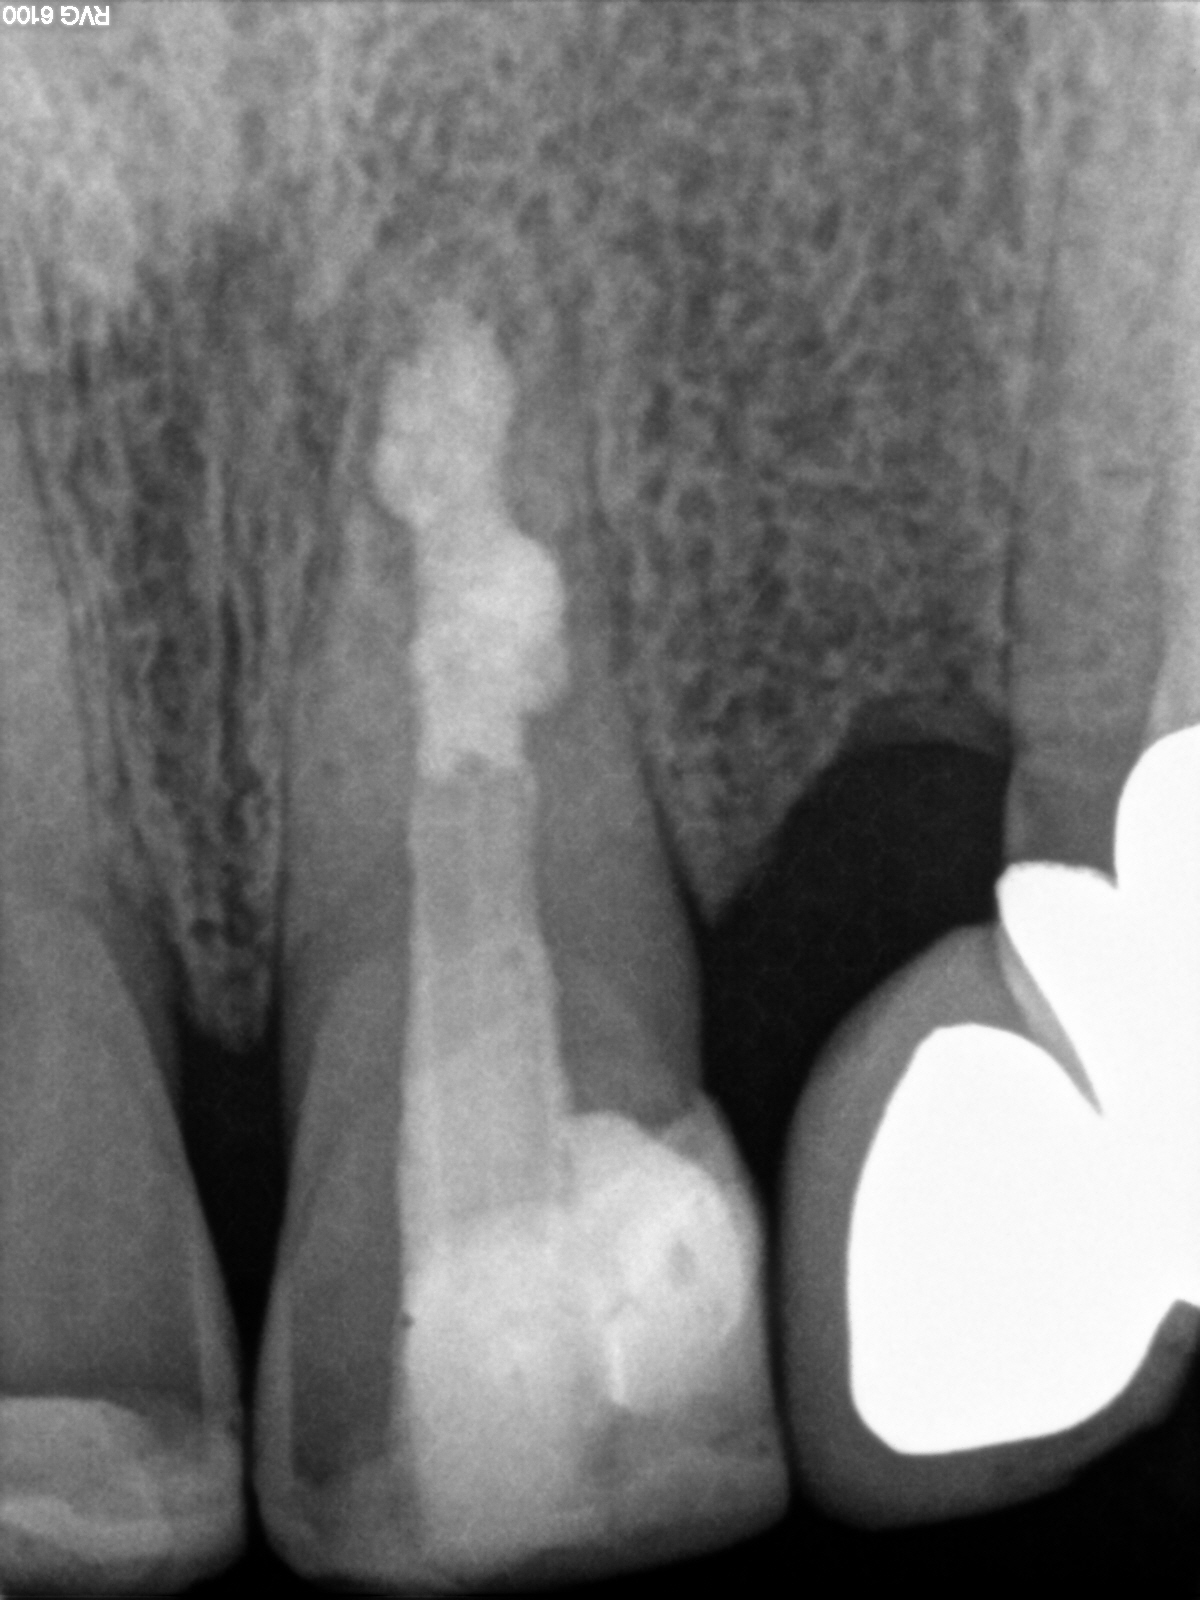

R51

1200 × 1600

24 Monatsrecall